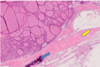

Know this image.

yeah.